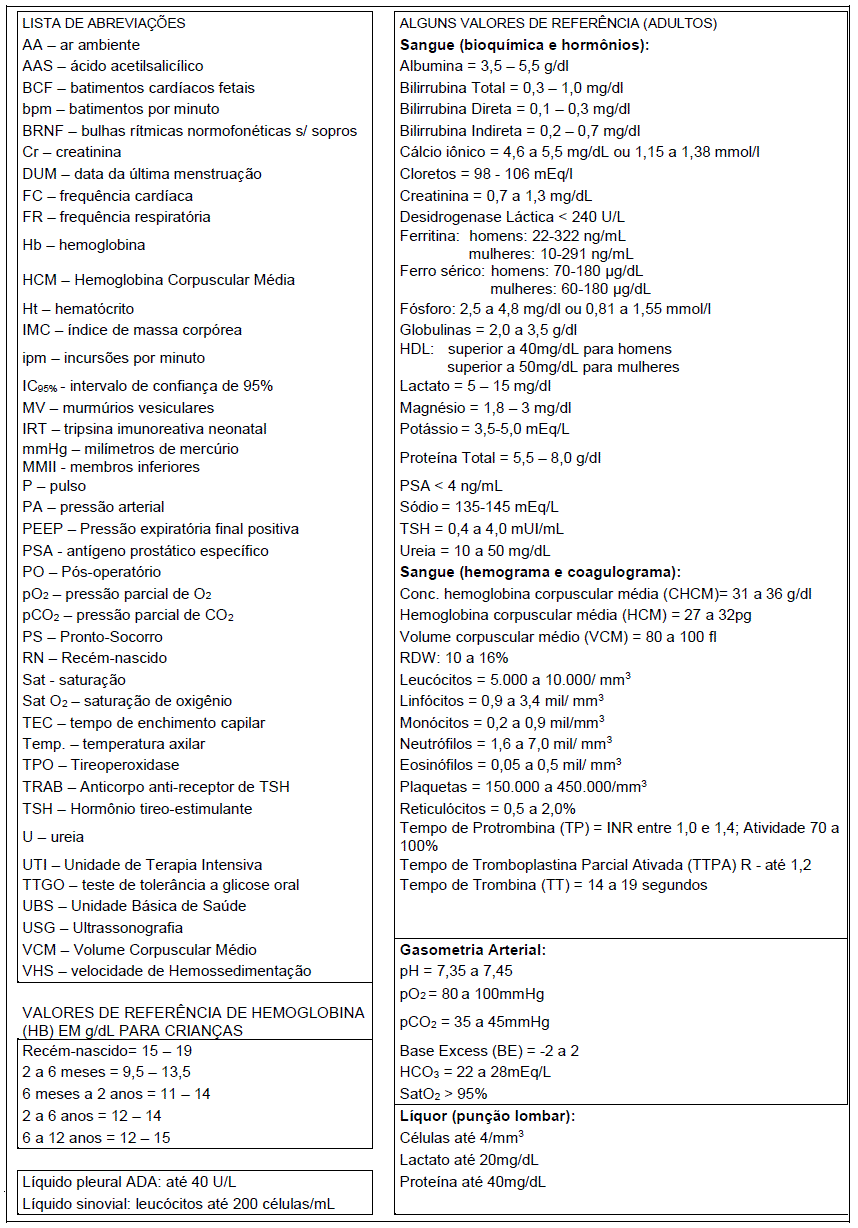

Mulher, 52 anos de idade, veio trazida ao Pronto-Socorro por queixa de cefaleia e uma crise tônico-clônica generalizada que ocorreu dois dias antes da admissão. Em seguida evoluiu com sonolência. Ao exame de admissão tem temperatura de 38ºC, PA 100x60 mmHg, FC: 112bpm e restante do exame clínico geral sem alterações. No exame neurológico, encontrava-se sonolenta, com abertura ocular aos estímulos verbais vigorosos, retirada inespecífica dos membros à dor, falando palavras desconexas, reflexos profundos globalmente vivos e reflexo cutâneo plantar em flexão bilateral. Também foram observadas algumas clonias em hemiface direita. Tomografia computadorizada de crânio mostrou uma hipoatenuação em lobo temporal esquerdo. Exames laboratoriais revelaram uma leucocitose de 13500 sem desvios à esquerda e um aumento da proteína C reativa. Foi então submetida a uma punção lombar para coleta de líquor cujo resultado foi de 41 células (66% de linfócitos, 32% de monócitos e 2% de neutrófilos), 48 hemácias, proteína de 59 mg/dL, glicose de 64 mg/dL e lactato de 25 mg/dL.

Mulher, 52 anos de idade, veio trazida ao Pronto-Socorro por queixa de cefaleia e uma crise tônico-clônica generalizada que ocorreu dois dias antes da admissão. Em seguida evoluiu com sonolência. Ao exame de admissão tem temperatura de 38ºC, PA 100x60 mmHg, FC: 112bpm e restante do exame clínico geral sem alterações. No exame neurológico, encontrava-se sonolenta, com abertura ocular aos estímulos verbais vigorosos, retirada inespecífica dos membros à dor, falando palavras desconexas, reflexos profundos globalmente vivos e reflexo cutâneo plantar em flexão bilateral. Também foram observadas algumas clonias em hemiface direita. Tomografia computadorizada de crânio mostrou uma hipoatenuação em lobo temporal esquerdo. Exames laboratoriais revelaram uma leucocitose de 13500 sem desvios à esquerda e um aumento da proteína C reativa. Foi então submetida a uma punção lombar para coleta de líquor cujo resultado foi de 41 células (66% de linfócitos, 32% de monócitos e 2% de neutrófilos), 48 hemácias, proteína de 59 mg/dL, glicose de 64 mg/dL e lactato de 25 mg/dL.